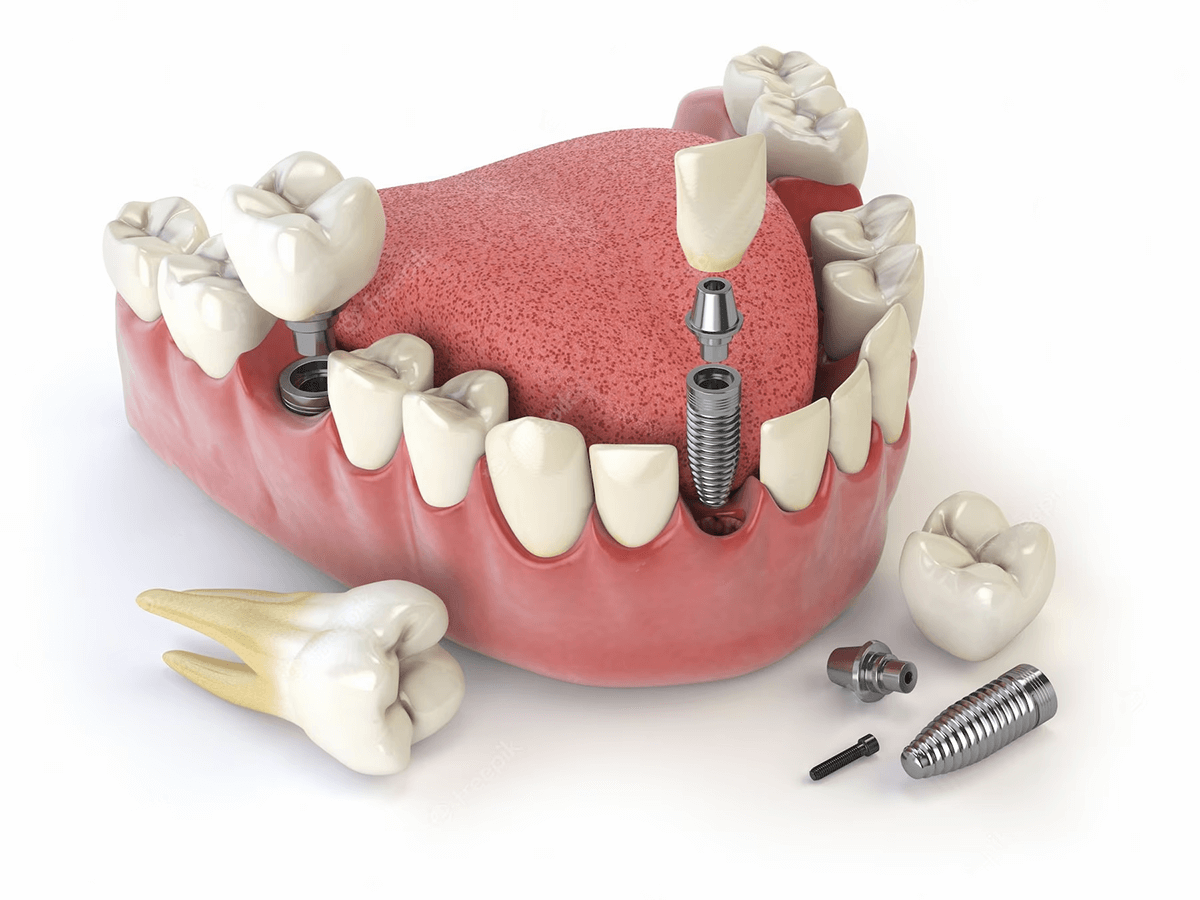

La única solución real a la pérdida de piezas dentales.

Los implantes dentales son una excelente opción para aquellas personas que han perdido uno o más dientes y desean recuperar su sonrisa y función oral. Sin embargo, es común tener preguntas sobre este procedimiento. Responderemos algunas de las preguntas más frecuentes sobre implantes dentales.

Restauración

Funcionalidad

Estética

Durabilidad

Recuperar tu sonrisa y disfrutar de una dentadura funcional es posible con los implantes dentales. Si has perdido uno o varios dientes, es importante determinar si eres apto para este tratamiento innovador que puede cambiar tu vida.

Suficiente densidad ósea

Los implantes dentales se fusionan con el hueso maxilar, por lo que es esencial tener una cantidad adecuada de hueso para sostener el implante. También se pueden realizar procedimientos como injertos óseos.